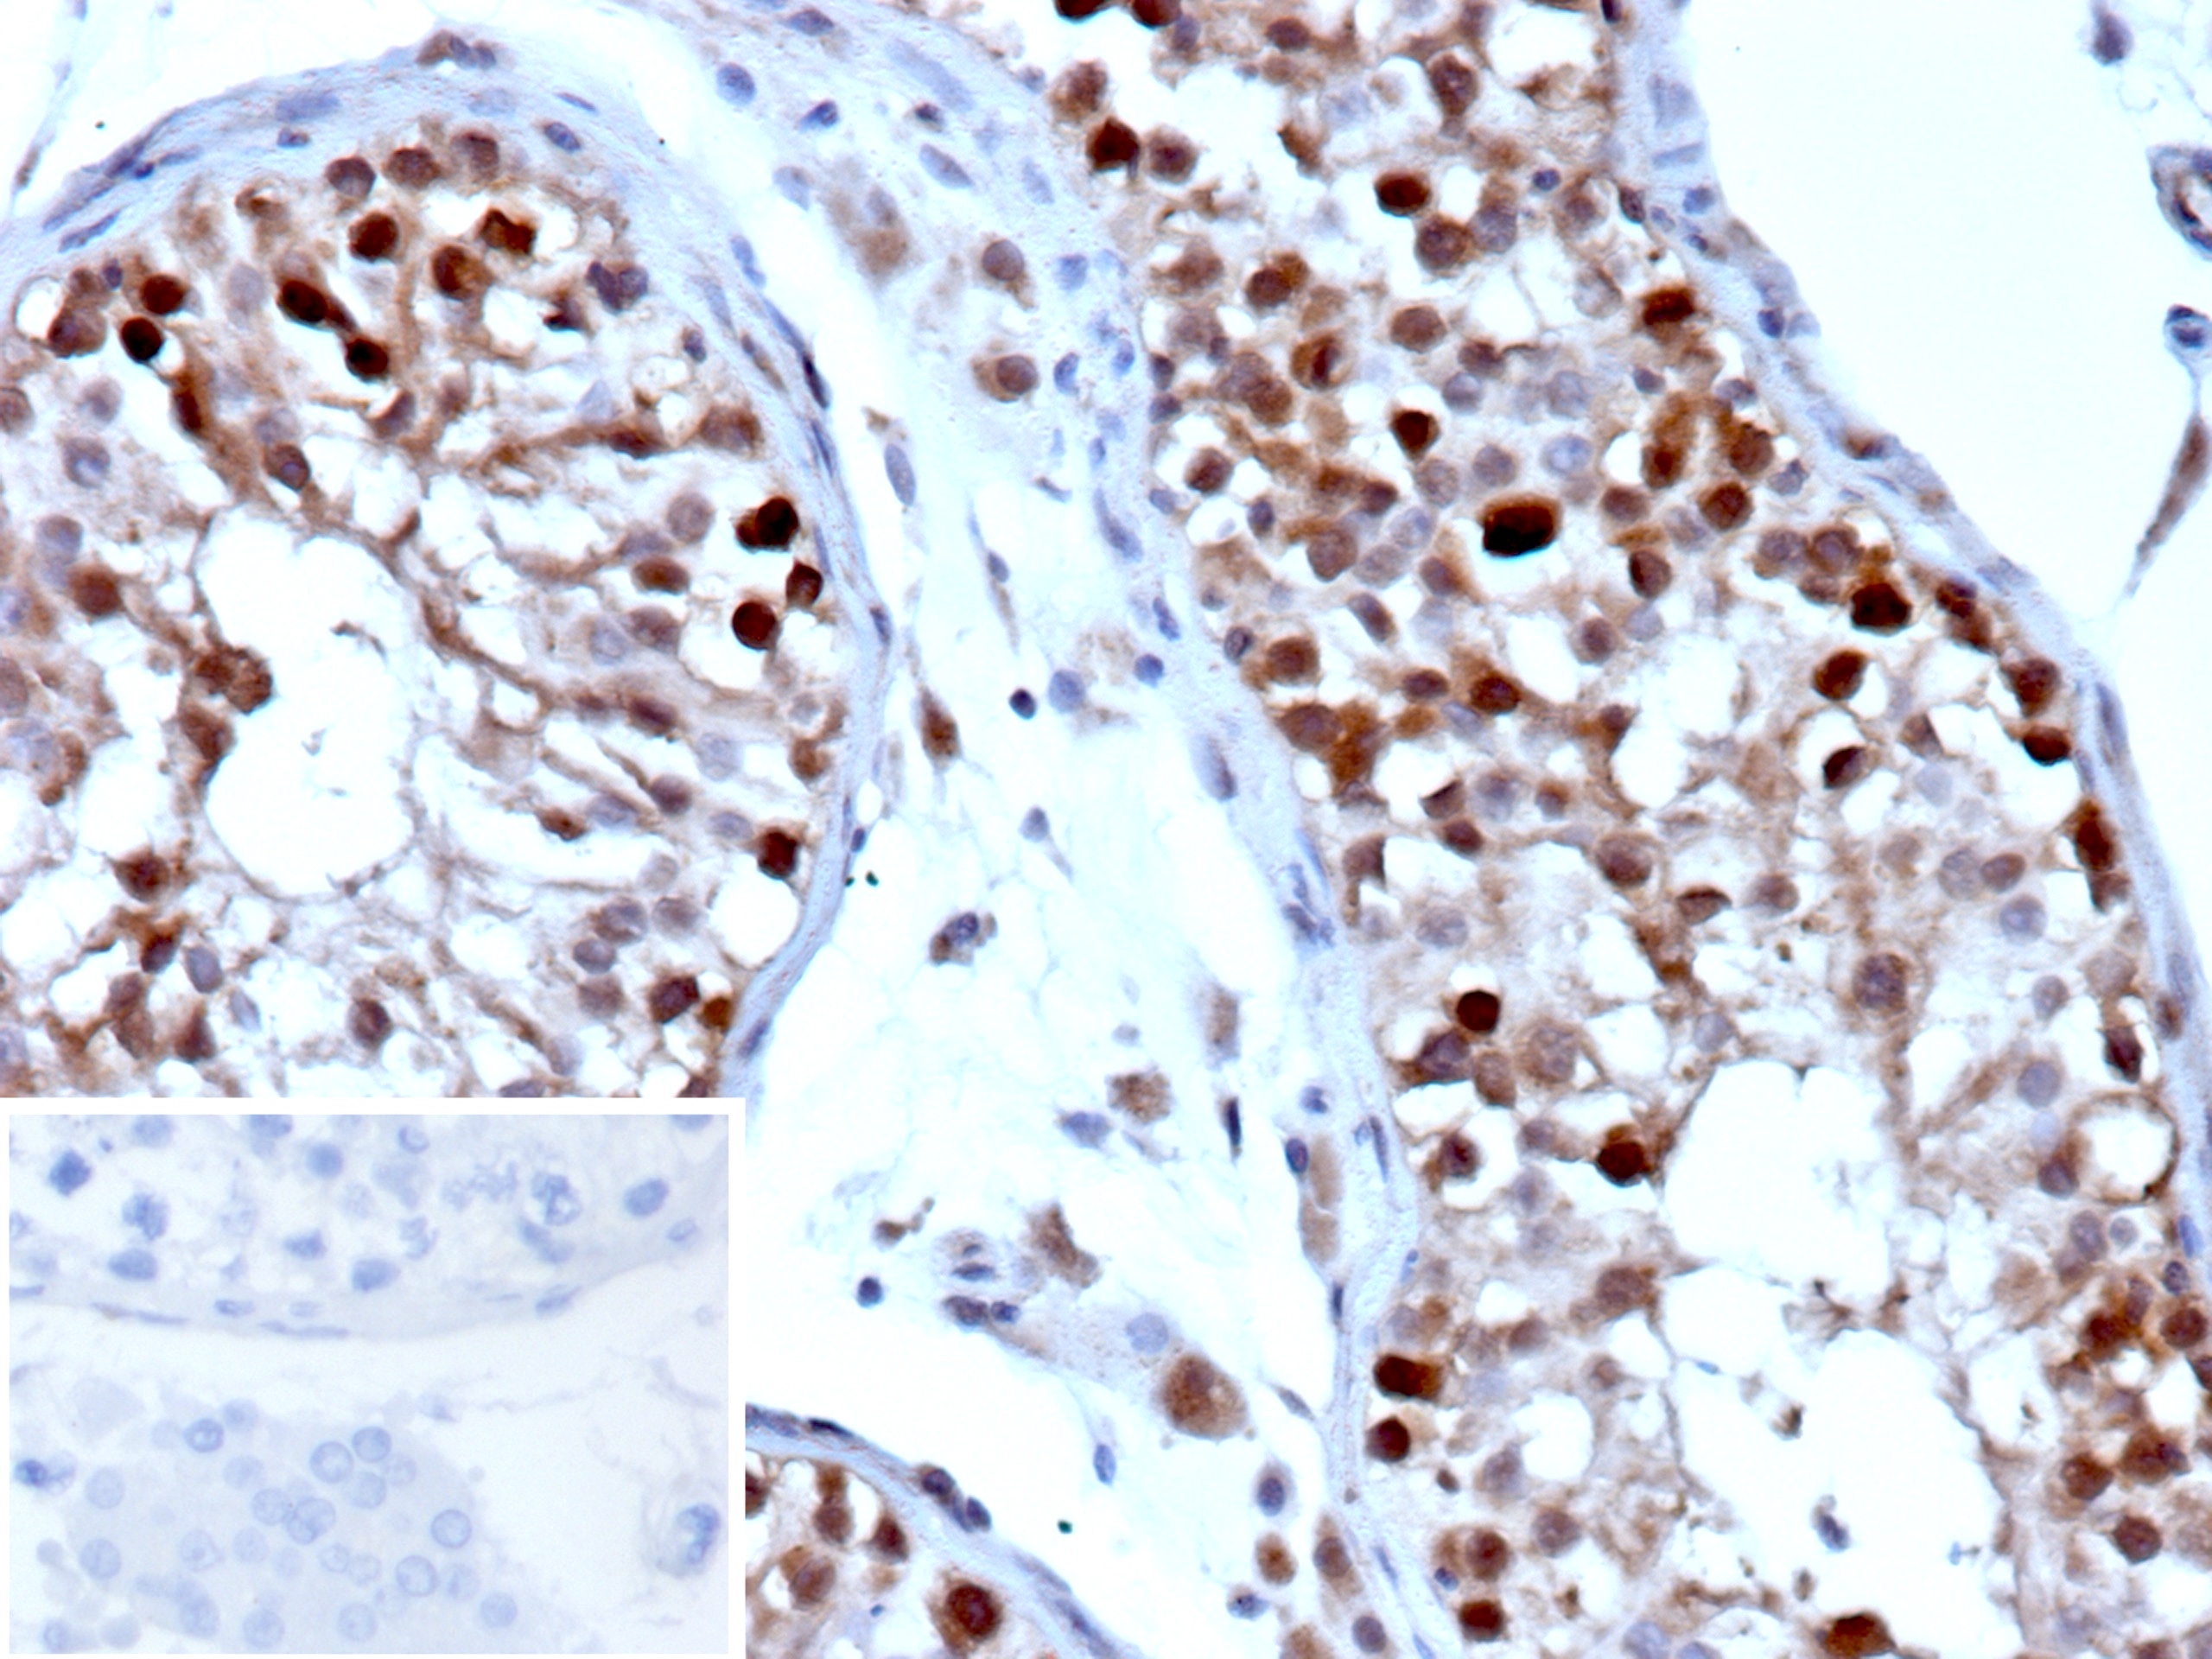

Immunohistochemistry (IHC)

1-2ug/ml

30 min at RT. Staining of formalin-fixed tissues requires heating tissue sections in 10mM Tris with 1mM EDTA, pH 9.0, for 45 min at 95°C followed by cooling at RT for 20 minutes

Human testicular carcinoma.